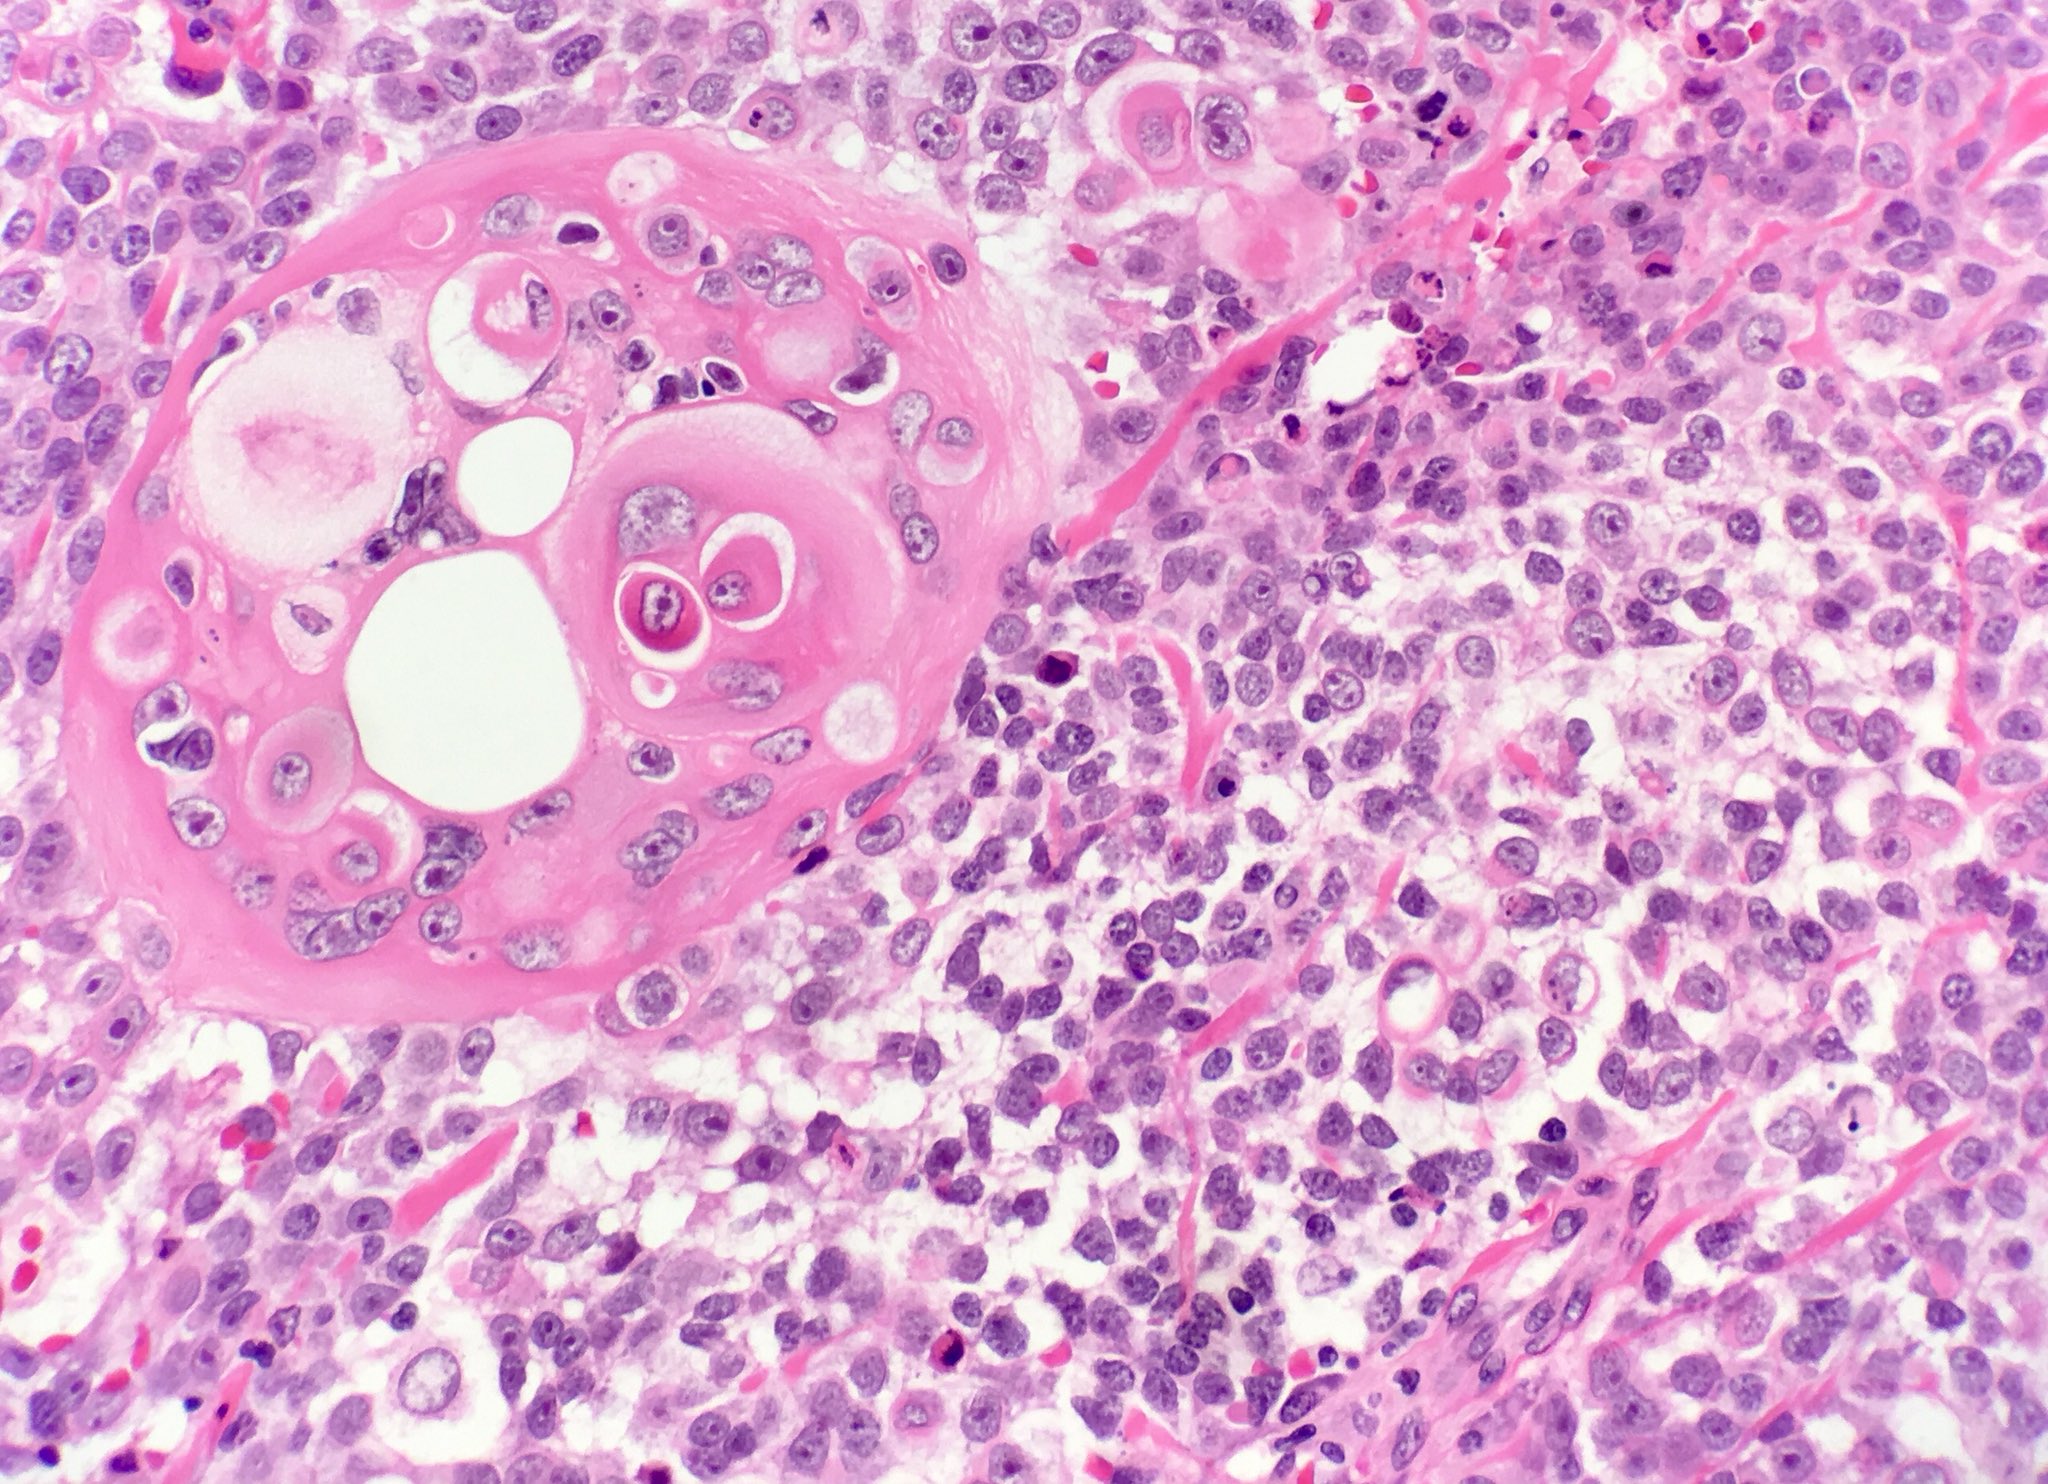

Key morphological features

- Infiltrating trabeculae of undifferentiatedcells

- Sudden squamous differentiation

- Desmoplastic stroma

- May have foci of squamous differentiation